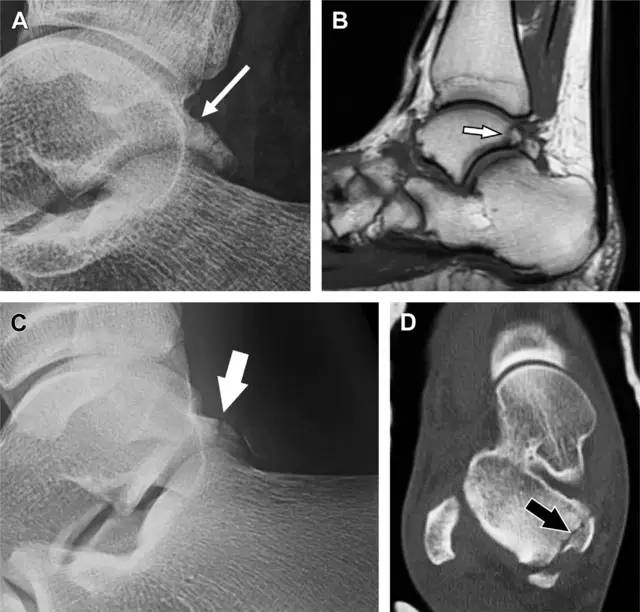

19 距骨后突骨折

距骨后突有内侧结节和外侧结节,距骨后突内侧结节撕脱性骨折常发生在背屈内旋的*力暴**作用下。严重跖屈时,胫骨后缘和跟骨挤压距骨后突外侧结节呈楔形,易发生粉碎性骨折。这些骨折细微且需与三角骨鉴别。侧位片观察距骨后突骨折最佳,常规拍片很难发现,当高度怀疑这种骨折又没法做 CT 时,建议加做多个角度的外旋斜位片(图 5)。

图 5 距骨后突骨折。侧位片(A)和 MRI 矢状位 T1 加权像(B)均示后外侧突的简单骨折(箭头),再次阅片时才发现 X 线片上的骨折;侧位片(C)和 CT 横断面图像示后内侧突的粉碎型骨折(箭头)